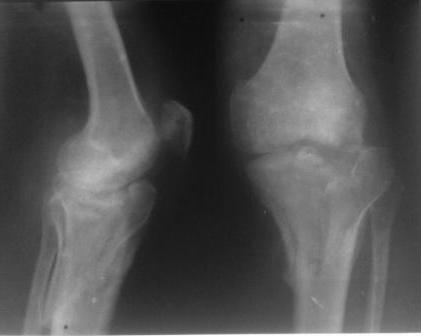

Обратился больной 46л. 3-месяца назад в каком-то городке Дальнего Востока упал с высоты, сделана Р-графия, наложена гипсовая повязка, от предложенной операции отказался и уехал домой, дальше где и как лечился, не говорит.

Ходит при помощи двух костылей, жалобы на боли при нагрузке, в покое и при движении, без нагрузке боли нет, разгибание 175 гр, сгибание 90 гр, симптомов повреждения связочного аппарата к/с не определяется, от предложенного артродеза пока отказывается.

Уважаемые коллеги! какие будут мнения по поводу лечения, эндопротез недоступен. Заранее благодарю! С уважением Абдурашид.

У пациента основной проблемой является импрессионый перелом наружного мыщелка, уже неправильно сросшийся, по-видимому. Аппаратом закрыто можно только подправить угол на уровне метадиафиза. Что

улучшит разве что внешний вид конечности, но не решит основной проблемы - грубой деформации суставной поверхности.